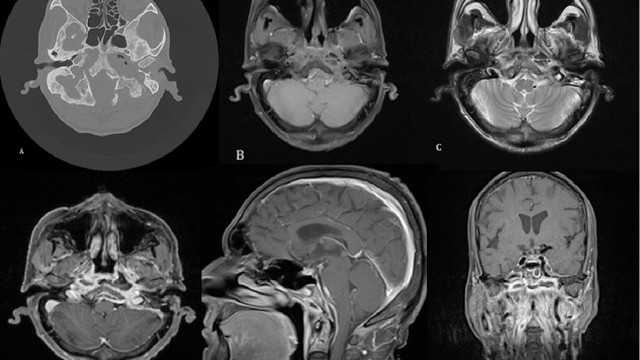

Viêm xương sọ là một tình trạng tương đối hiếm gặp, thường xảy ra như một biến chứng của nhiễm trùng tai hoặc xoang tiến triển ở những bệnh nhân đái tháo đường hoặc bị suy giảm miễn dịch. Chẩn đoán viêm xương sọ bằng lâm sàng và cận lâm sàng, tuy nhiên bệnh thường được chẩn đoán muộn. Thuốc kháng sinh dài hạn kết hợp với phẫu thuật cắt bỏ mô trong các trường hợp nặng là phương pháp điều trị chính. Viêm xương sọ là tình trạng nguy hiểm đến tính mạng nếu không được chẩn đoán và điều trị sớm.